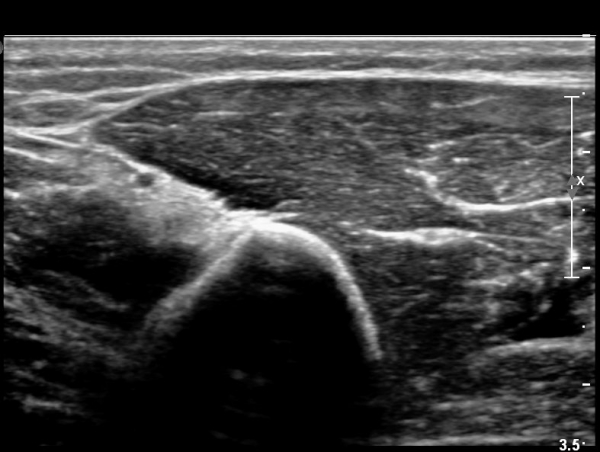

¿ä°ñ °í¶û¿¡¼­ ¿ä°ñ½Å°æ Ⱦ´Ü¸é°Ë»ç»ó ¿ä°ñ½Å°æÀÇ °æ¹ÌÇÑ Àú¿¡ÄÚ ºÎÁ¾ÀÌ °üÂûµÈ´Ù(»çÁø 2).

ŽÃËÀÚ¸¦ Á¶±Ý ¸»´ÜÀ¸·Î À̵¿ÇÏ´Ï ¿ä°ñ½Å°æ Àú¿¡ÄÚ ºÎÁ¾ÀÌ ´õ¿í ¶Ñ·ÈÇѵ¥(»çÁø 2),